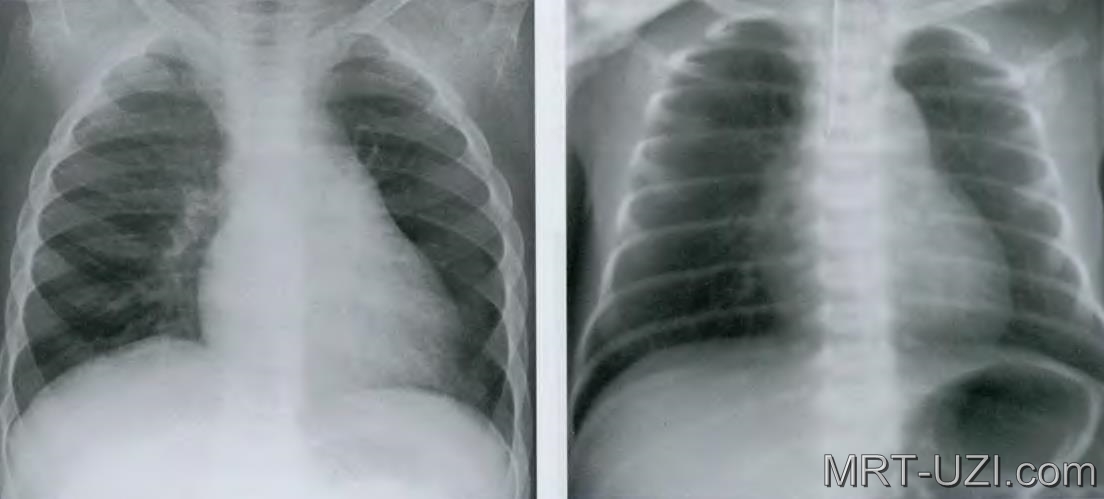

Рентген легких в двух проекциях

Два основных типа проекций: прямая (передне-задня) и боковая (боковая).

Прямая (передне-задня) проекция

В прямой проекции рентгеновский луч проходит через переднюю поверхность тела пациента и попадает на пленку, расположенную сзади. Этот метод позволяет оценить состояние всех отделов легких и диафрагмы.

Боковая (боковая) проекция

При боковой проекции рентгеновский луч проходит через боковую поверхность тела пациента. Этот метод позволяет получить информацию о задних отделах легких, а также о состоянии позвоночника и ребер.